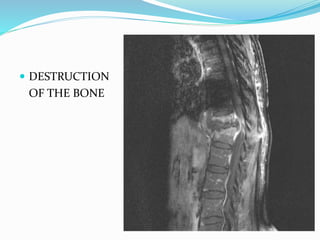

2. DESTRUCTION OF VERTEBRAL BODY

EROSIONS AND WEDGING

BONE DESTRUCTION

 DESTRUCTION

OF THE BONE

FINDINGS  1. REDUCTIONOF DISC SPACE- EARLY SIGN • COMPARE WITH NORMAL LATERAL X-RAY IS BETTER IMPORTANCE : SECONDARIES TO BONES USUALLY PRESERVE THE DISC 2. DESTRUCTION OF VERTEBRAL BODY EROSIONS AND WEDGING 3. DEFORMITY : DEPEND ON THE NO. OF VERTEBRA AFFECTED